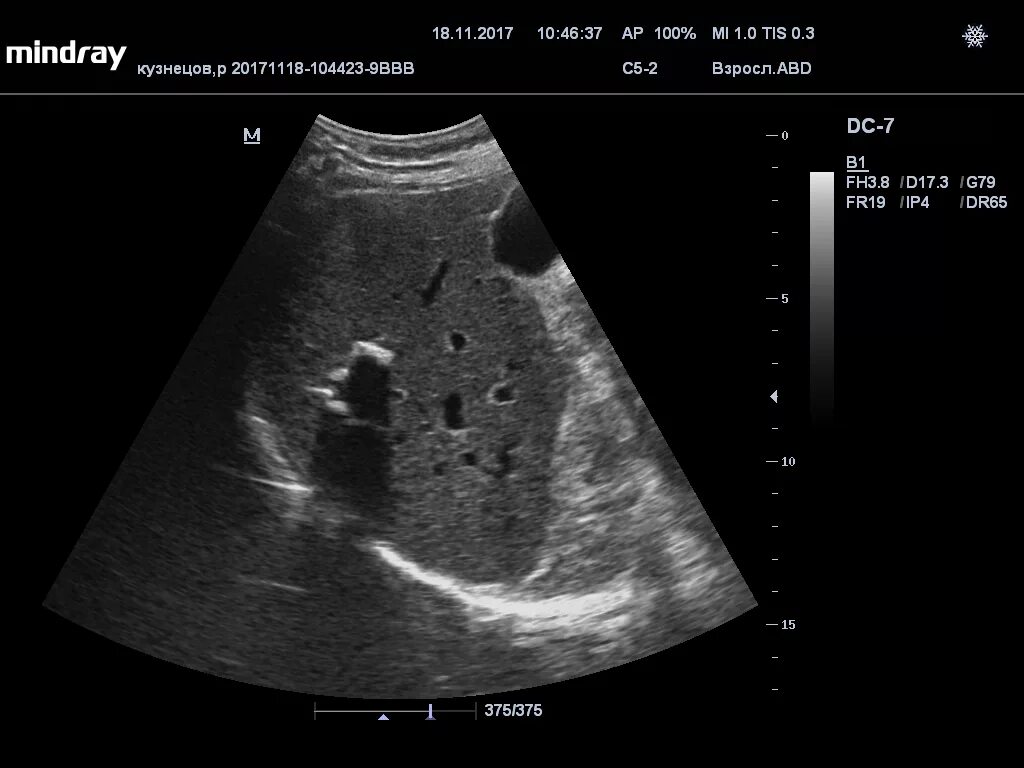

Метастазы в печени на узи прогноз